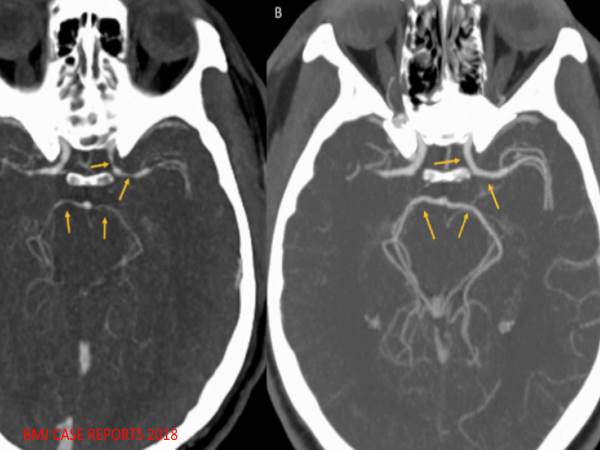

इसे थंडरक्लैप कहते हैं, जिसकी वजह से अचानक सिर में तेज दर्द होना लगता है, जो खून को मस्तिष्क में ले जाता है। ऐसी स्थिति को सेरेब्रल वासोकोनट्रक्शन सिंड्रोम (आरसीवीएस) कहा जाता है। कैरोलाइना रीपर खाने की बाद शख्स की स्थिति इतनी बुरी थी कि उसे कई न्यूरोलॉजिकल परिस्थितियों के लिए परीक्षण किया गया था, हालांकि परिणाम नकारात्मक ही हुए।